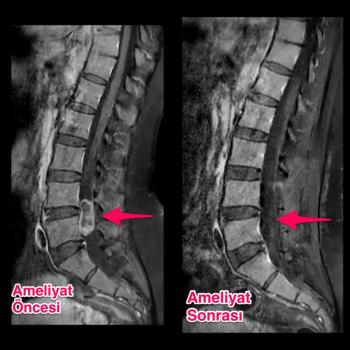

Bel Fıtığı (Lomber disk hernisi)

Disk materyali iki omur cismi arasında dışarıda görece olarak daha sert bir kılıf, içeride ise jel kıvamında yumuşak doku kısımlarından oluşur. Bir y...

Günümüzdeki modern tanı yöntemlerinden olan Manyetik Rezonans(MR) ile bel fıtığı teşhisi kolaylıkla konulmakta ve derecesi belirleneb...

Bel fıtığı ameliyatlarındaki amaç fıtıklaşan diskin temizlenesi ve sinir üzerindeki basıyı kaldırmaktır.Açık diskektomi: Genellikle genel anestezi ...